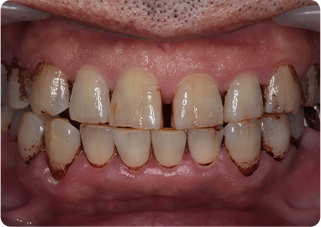

セラミッククラウン症例②

術前

仮歯

術後

| 主訴 | 前歯を綺麗にしたい、隙間が気になる |

|---|---|

| 治療期間/回数 | 4ヵ月、6回 |

| 価格(税込) | 792,000円(税込) |

| リスク・副作用 | セラミック破損の可能性 |

| ポイント | 仮歯で歯ぐきの状態を整え、自然な色、形となるようにオーダーメイドでセラミックを盛り、クラウンを作製した。 |